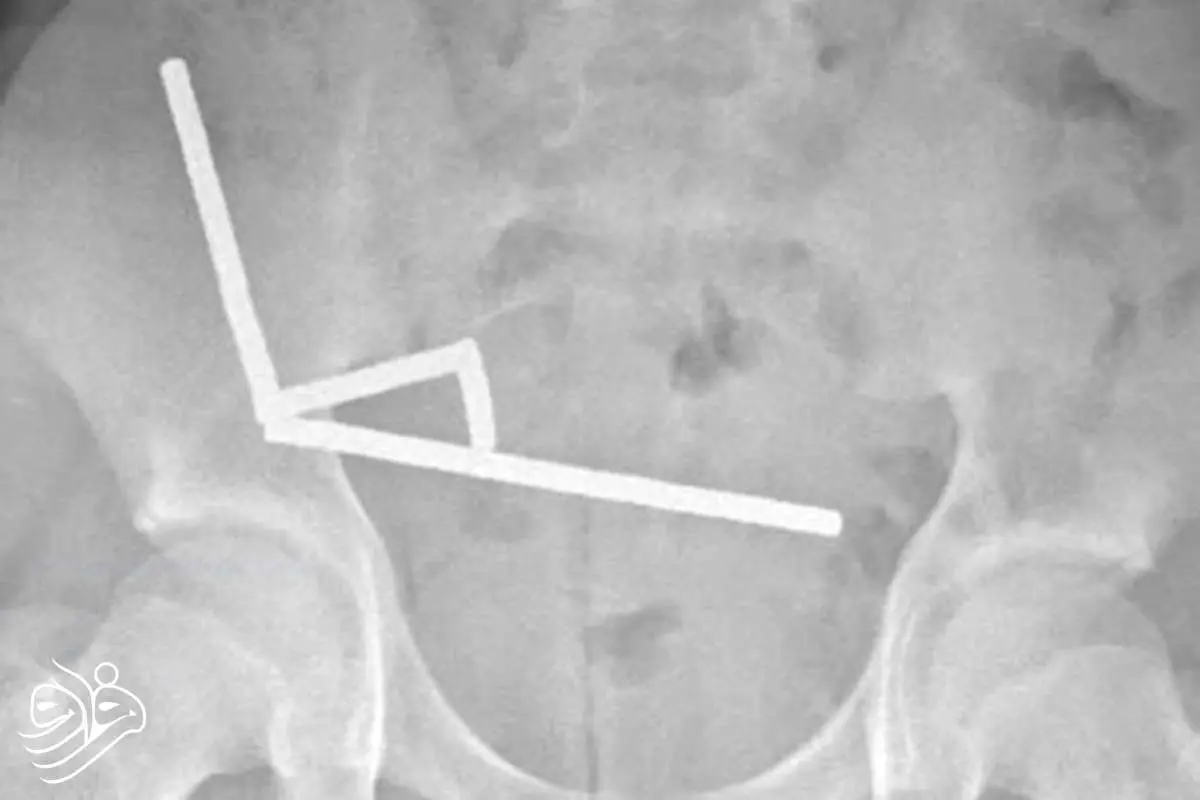

تصاویر رادیولوژی، چهار زنجیره بلند از آهنرباها را در بخش‌های جداگانه روده نشان داد. این ذرات فلزی کوچک درون بدن به هم متصل شده و باعث انسداد، پارگی و مرگ بخشی از بافت روده بر اثر فشار مغناطیسی شدند. در نهایت، پزشکان ناچار شدند بخشی از روده را خارج کنند.به گفته تیم درمان، وضعیت عمومی این نوجوان پس از عمل جراحی رضایت‌بخش است و او پس از هشت روز بستری، از بیمارستان مرخص شد.

زنجیره‌های آهنربایی در شکم نوجوان نیوزیلندی